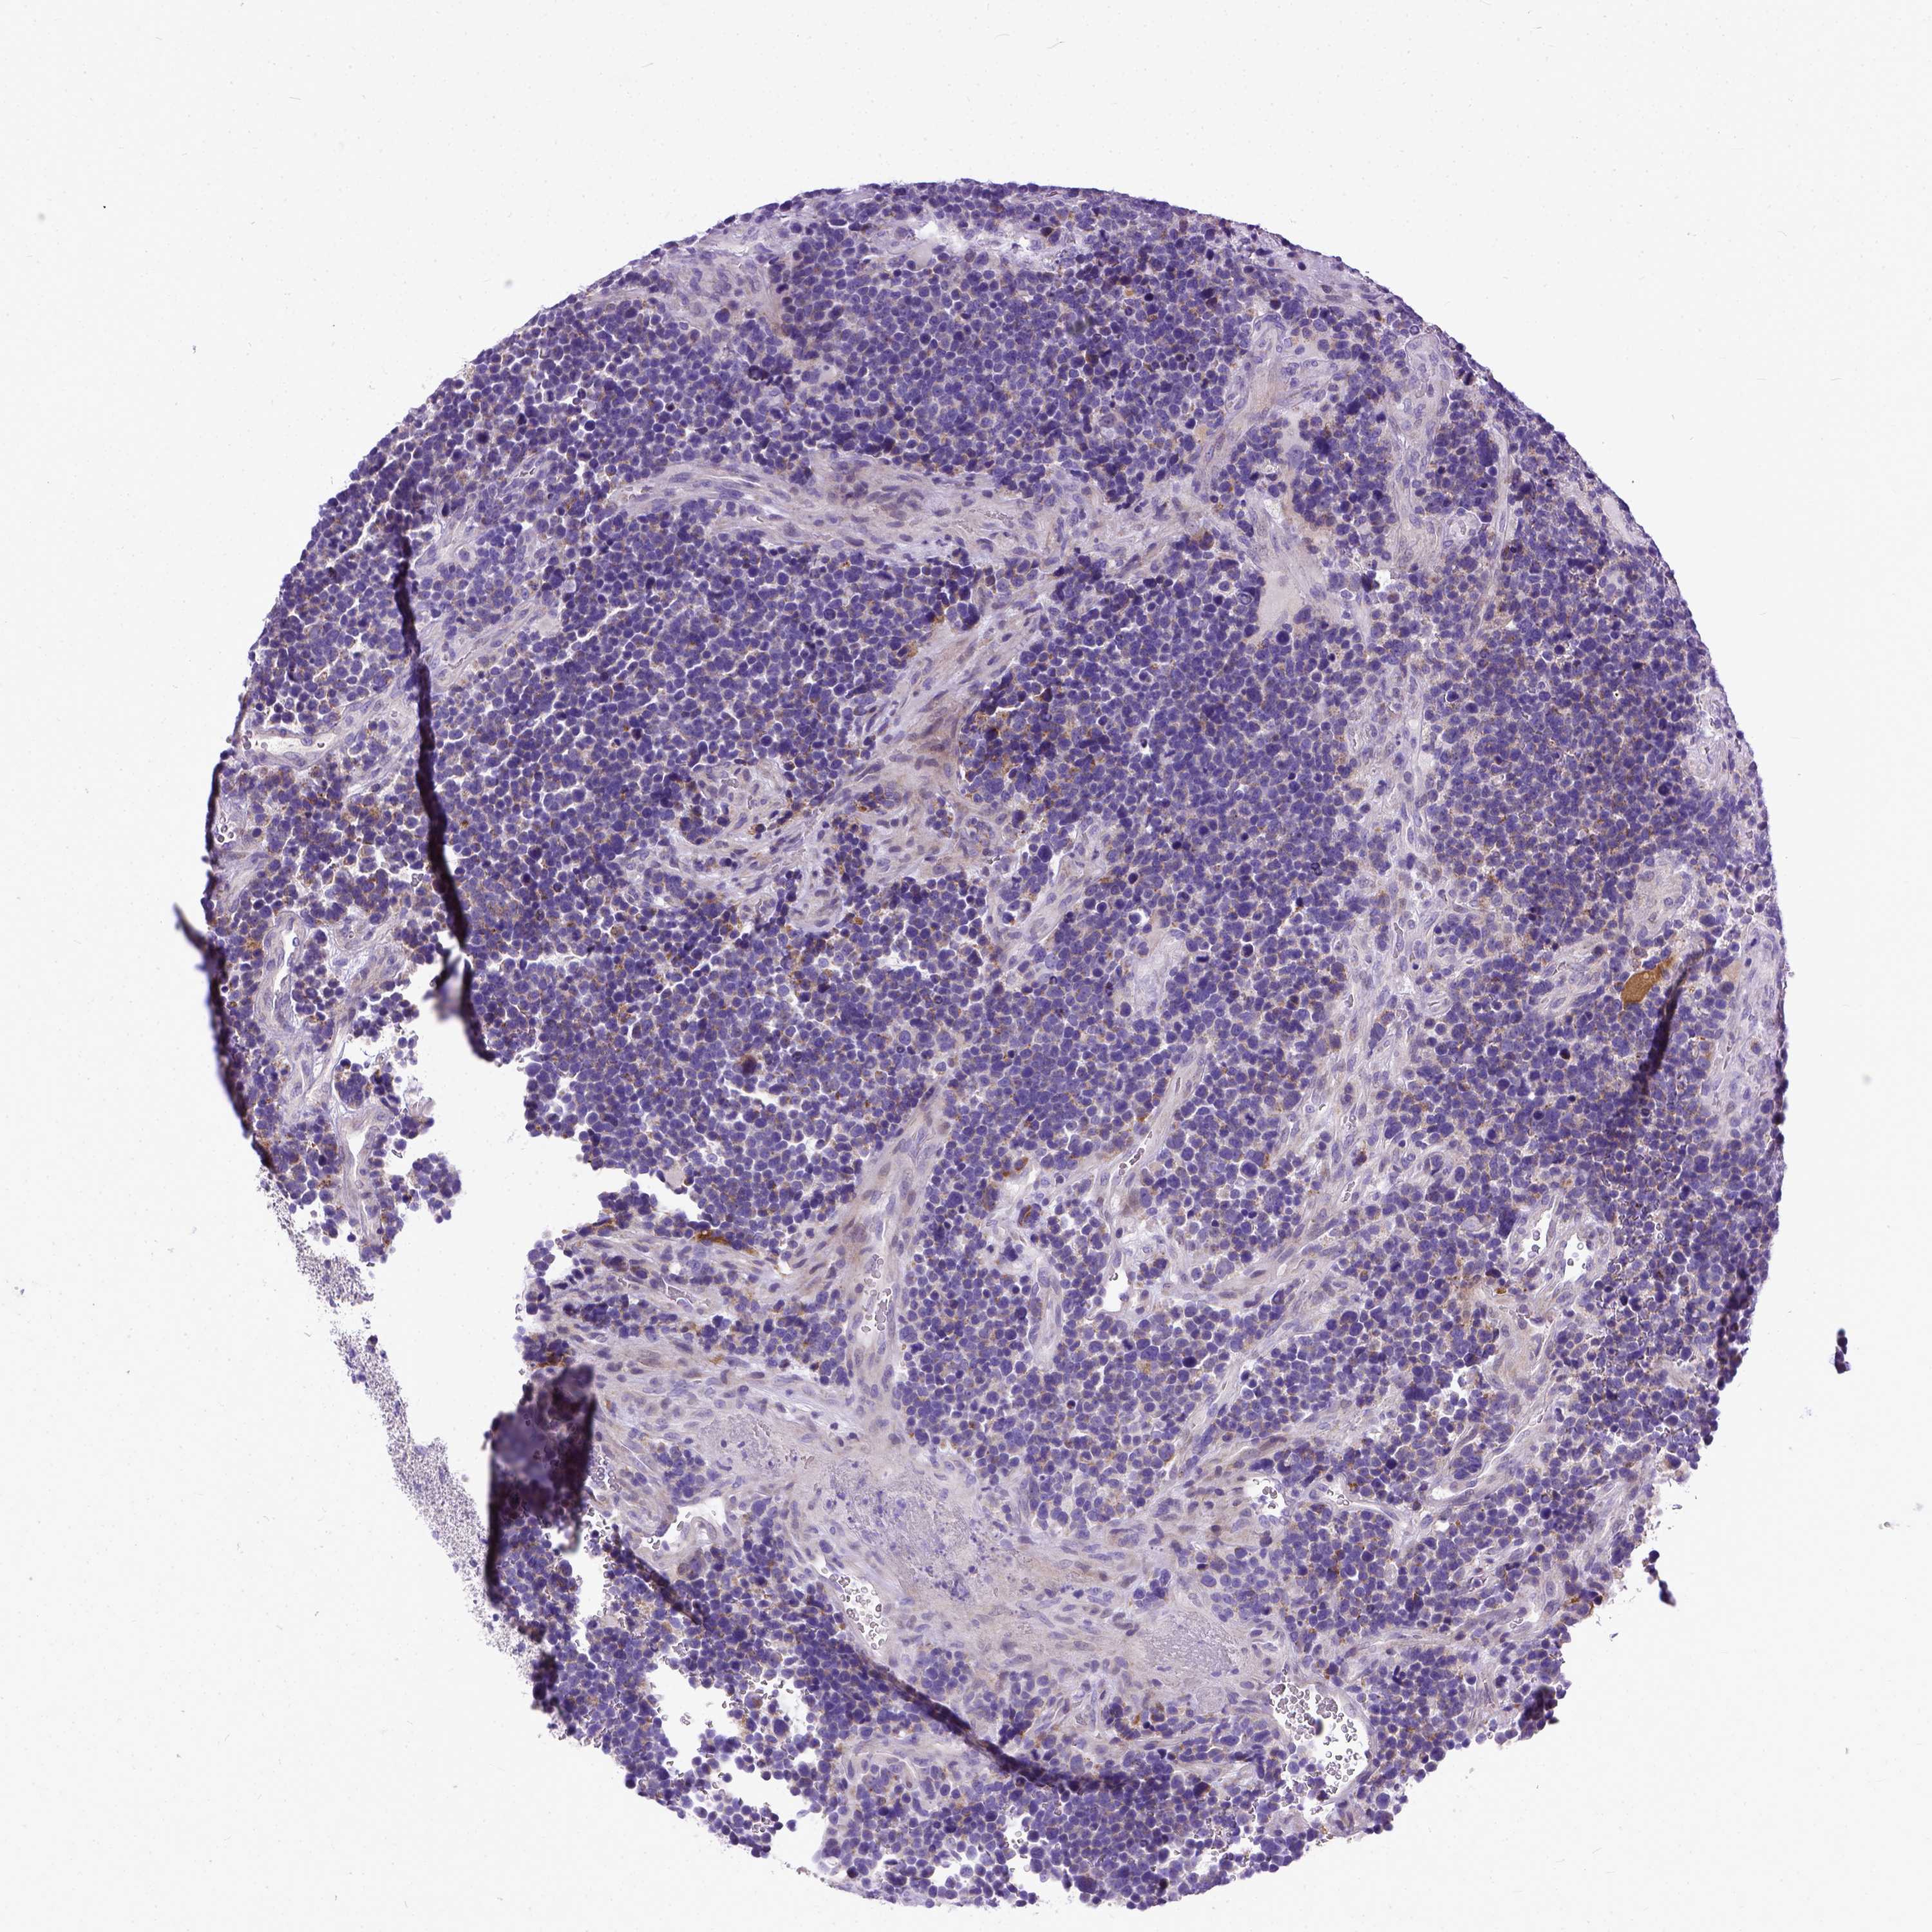

GLIOMA - Protein expressioni

A mouse-over function shows sample information and annotation data. Click on an image to view it in a full screen mode. Samples can be filtered based on level of antibody staining by selecting one or several of the following categories: high, medium, low and not detected. The assay and annotation is described here.

Note that samples used for immunohistochemistry by the Human Protein Atlas do not correspond to samples in the TCGA dataset.

Antibody stainingi

Antibody staining in the annotated cell types in the current human tissue is reported as not detected, low, medium, or high, based on conventional immunohistochemistry profiling in selected tissues. This score is based on the combination of the staining intensity and fraction of stained cells.

Each image is clickable and will lead to virtual microscopy that enables deeper exploration of all samples and also displays staining intensity scores, fraction scores and subcellular localization as well as patient and tissue information for each sample.

Antibody HPA035024

Staining

High

Medium

Low

Not detected

Intensity

Strong

Moderate

Weak

Negative

Quantity

>75%

75%-25%

<25%

None

Location

Nuclear

Cytoplasmic/membranous

Cytoplasmic/membranous,nuclear

Glioma, malignant, Low grade

Glioma, malignant, High grade